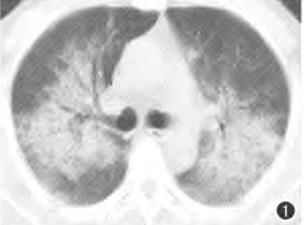

2.年轻女性,发热,气促,咳嗽,CT如下:

病灶也是略呈蝶羽征。

患者发热,咳嗽,明显呼吸困难,H1N1阳性。

重型甲流病毒性肺炎。